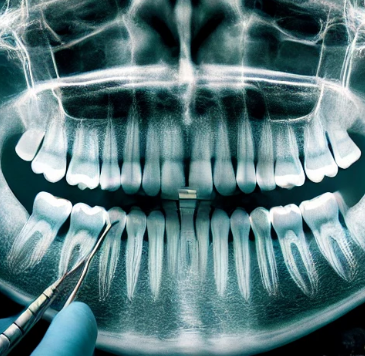

1. 진단 및 계획 수립

어금니 임플란트를 시작하기 전에, 정확한 진단이 필수입니다. 치과 전문의는 X-레이, CT 스캔 등을 통해 환자의 구강 상태를 분석하고, 어금니 뿌리와 잇몸 상태를 확인합니다. 또한, 환자의 뼈 상태를 확인하여 뼈 이식이 필요한지 여부를 판단합니다. 이 진단 과정이 끝나면 개별 환자에게 맞는 시술 계획을 수립하게 됩니다.